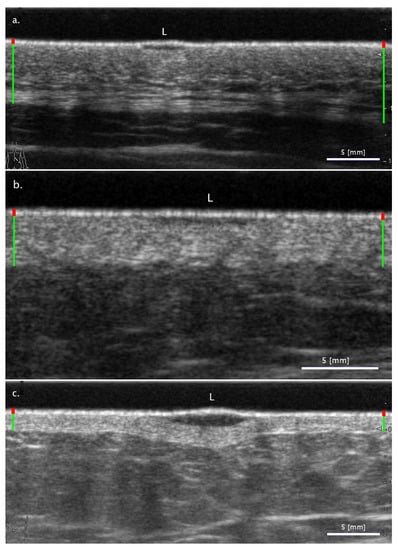

3.2.1. Cases When FA Fails While SA Methods Perform Correctly

3.2.2. Cases When the Two SA Methods Return Different Classifications

3.2.3. Cases When the SA Methods Both Fail While the FA Method Performs Correctly